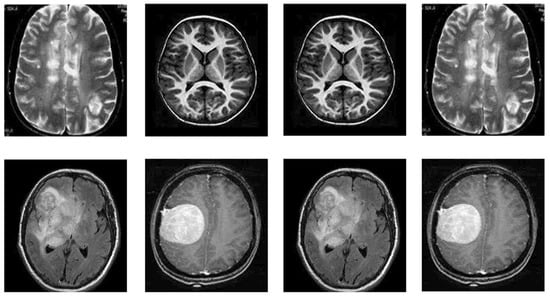

4.2. Dataset

This section includes comprehensive details regarding the dataset utilized for BTD. The research dataset utilized for detecting brain tumors in this study is adopted from the BTD-MRI dataset, which is easily accessible on Kaggle [31]. The dataset comprises two collections. The first collection of the dataset has 1500 MRI images without tumors, whereas the second collection has 1500 tumor images. We used 80% of the data for training and 20% (remaining) for testing the TumorResNet model. More specifically, we used all 3000 images of the standard Kaggle BTD-MRI dataset [28] for this experiment, where 2400 images (1200 tumorous and 1200 healthy images) were utilized for model training and the rest 600 images (300 tumorous and 300 healthy images) for testing. Some representative samples from the dataset are shown in Figure 2.

Figure 2. Samples of BTD-MRI dataset, upper row: No tumor examples and lower row: tumorous images examples.